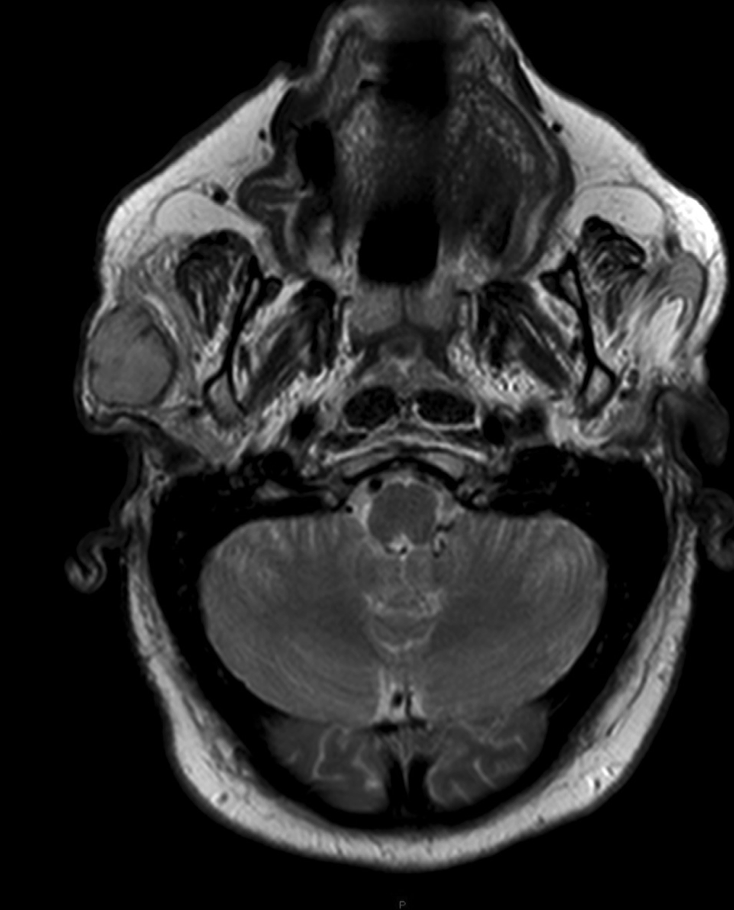

- The parotid gland is the most common affected gland by MASC

- The majority of MASC arise from the parotid gland;

- Accounting for two thirds of the reported cases